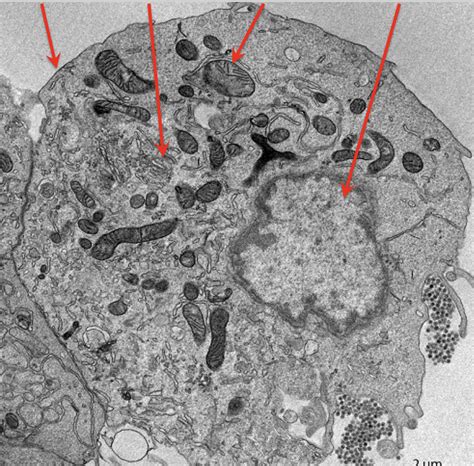

Now, let’s get into the really fascinating stuff: the life cycle of Pseuoschistosome side 13 . Parasites are masters of survival, and their life cycles are often incredibly complex, designed to ensure they can reproduce and spread effectively. For Pseuoschistosome side 13, this typically involves at least two different host species. Usually, there’s an intermediate host, which is often a snail or another mollusk, and a definitive host, which is where the parasite reaches sexual maturity and reproduces, often a vertebrate like a fish, bird, or even a mammal. The cycle might start with eggs being shed into the environment, perhaps in water or feces. These eggs hatch into a larval stage, which then needs to infect the intermediate host – let’s say, a specific type of snail. Inside the snail, the parasite undergoes significant development and multiplication, often through several more larval stages. This is where the ‘side 13’ might be particularly relevant, as certain genetic variations could influence its infectivity or development within specific snail species. Once it’s developed sufficiently within the snail, a new larval form emerges, ready to infect the definitive host. This stage is often the one that poses a potential risk. For instance, if humans accidentally ingest contaminated water or come into contact with infected intermediate hosts, they could become infected. Inside the definitive host, the parasite matures into an adult worm, mates, and lays eggs, thus completing the cycle and perpetuating the species. Understanding each step – from egg to larva to infective stage – is crucial for figuring out how to break the cycle. This might involve controlling the snail population, improving sanitation to prevent contamination, or educating communities about the risks. The ‘side 13’ designation can be vital here, as different strains might prefer different hosts or have varying levels of infectivity, requiring tailored control strategies. It’s a delicate dance of adaptation and survival, and studying this cycle gives us the upper hand in preventing infections. The sheer ingenuity of these organisms in navigating their multi-host existence is truly remarkable, showcasing nature’s relentless drive for continuation. Each stage is a critical bottleneck, and Pseuoschistosome side 13 has evolved to overcome them all.